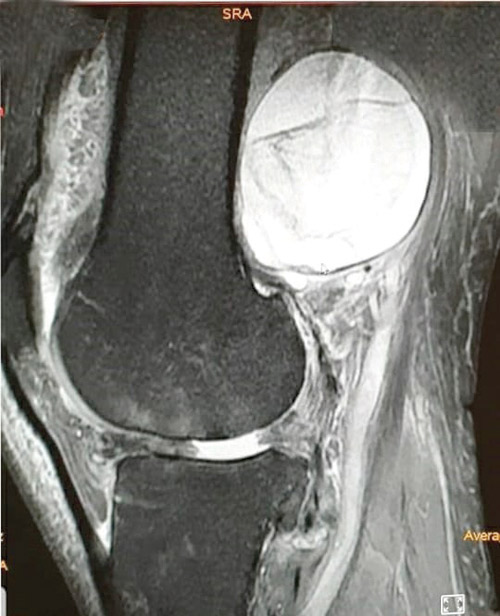

والذي أضاف بأن المريض وصل للعيادة وهو يشكو من مضاعفات عدة في منطقة الركبة، حيث خضع لعدد من الفحوصات الدقيقة منها الفحص السريري وإجراء التحاليل المخبرية والتصوير بالرنين المغناطيسي (M.R.I) بالصبغة، وقد أكدت نتائج الفحوصات وجود ورم دائري كبير بقطر يصل إلى أكثر من 10 سم متمركز في المنطقة الخلفية للركبة ومتصلاً بالعظم مزيحاً الحزمة الوعائية العصبية.